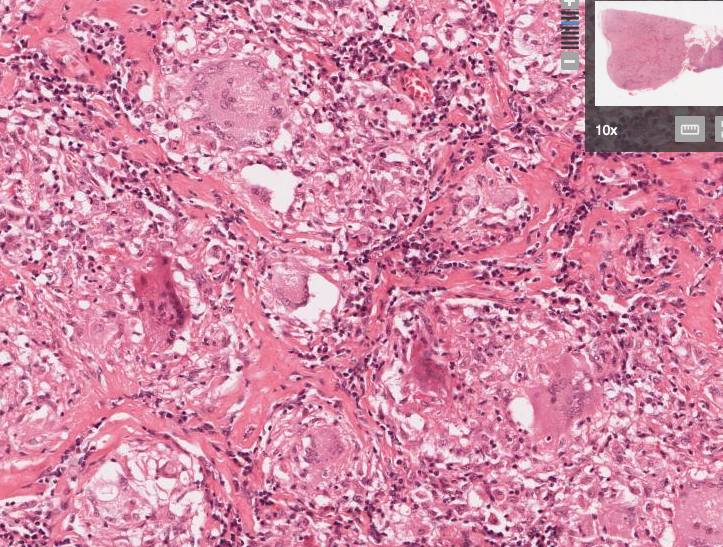

Sarcoidosis - giant cells, non-caseating granuloma, epitheloid cells

Hypersensitivity pneumonitis - interstitial pneumonitis, non-caseating granulomas